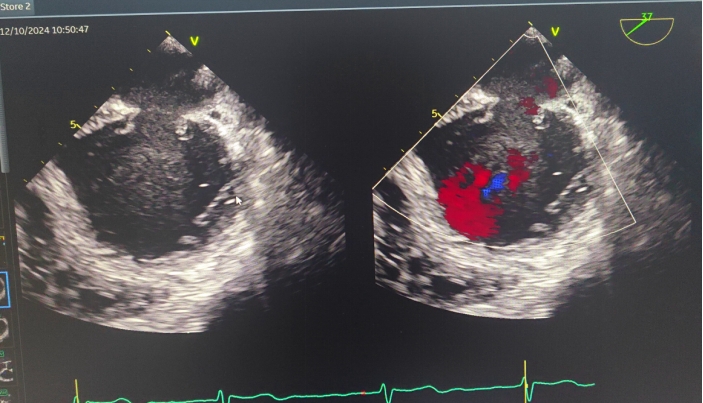

患者,男,81岁高龄。反复双下肢水肿8年有余,头晕、心慌3年多,还有慢阻肺、缺铁性贫血等病史。心脏彩超显示:前叶长度2.3cm,后叶长度0.9cm,瓣口面积5.5cm²,无有效对合高度,病变宽度达18mm,手术难度呈指数级攀升,情况不容乐观。

一切准备就绪后,麻醉手术中心专家凭借精湛技艺,让患者全程处于平稳麻醉状态,为手术筑牢安全根基。超声诊断科医生犹如“透视眼”,实时提供精准影像指引,让手术操作有的放矢。术中,陈玺全副主任团队在2区植入一枚长宽夹后,棘手状况再现。由于瓣叶张力过大,团队果断调整策略,以特定角度释放二尖瓣夹。当夹子关闭至-30°时,奇迹发生,反流降至1+,术后跨瓣压差仅为1mmHg,手术效果惊艳众人。